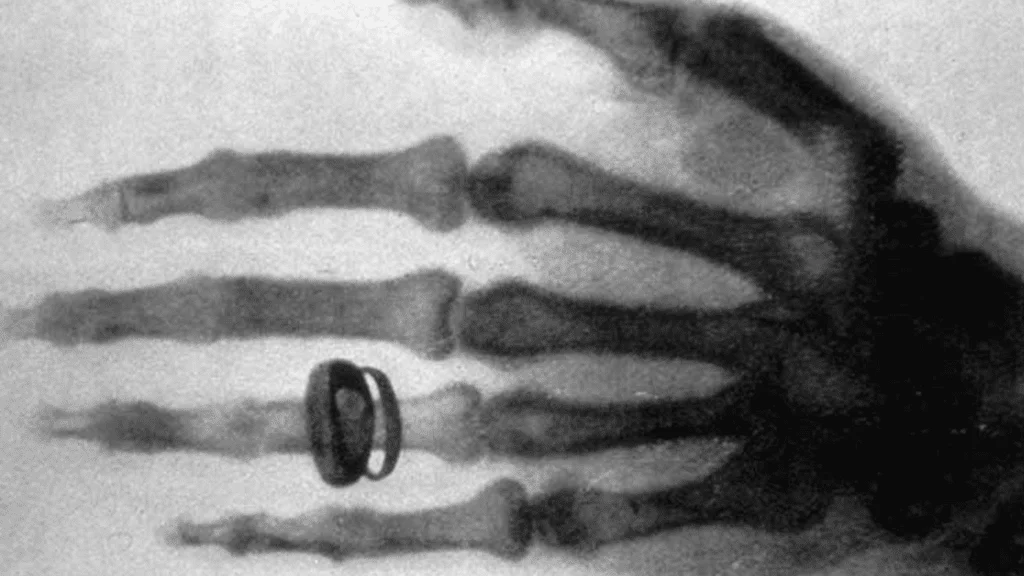

Vynálezy doprovázejí lidstvo po celou dobu jeho existence, neboť umožňují pokrok. Koncem 19. století nastaly obzvlášť přínosné časy, jelikož byla věnována velká pozornost fyzice. Otevřela se tak cesta k mnohem složitějším a převratnějším výzkumům. Jedním z nich byl Röntgenův objev rentgenových paprsků, čímž se výrazně posunula medicína.

Princip, který vedl k zavedení rentgenu, Wilhelm Röntgen objevil náhodou.